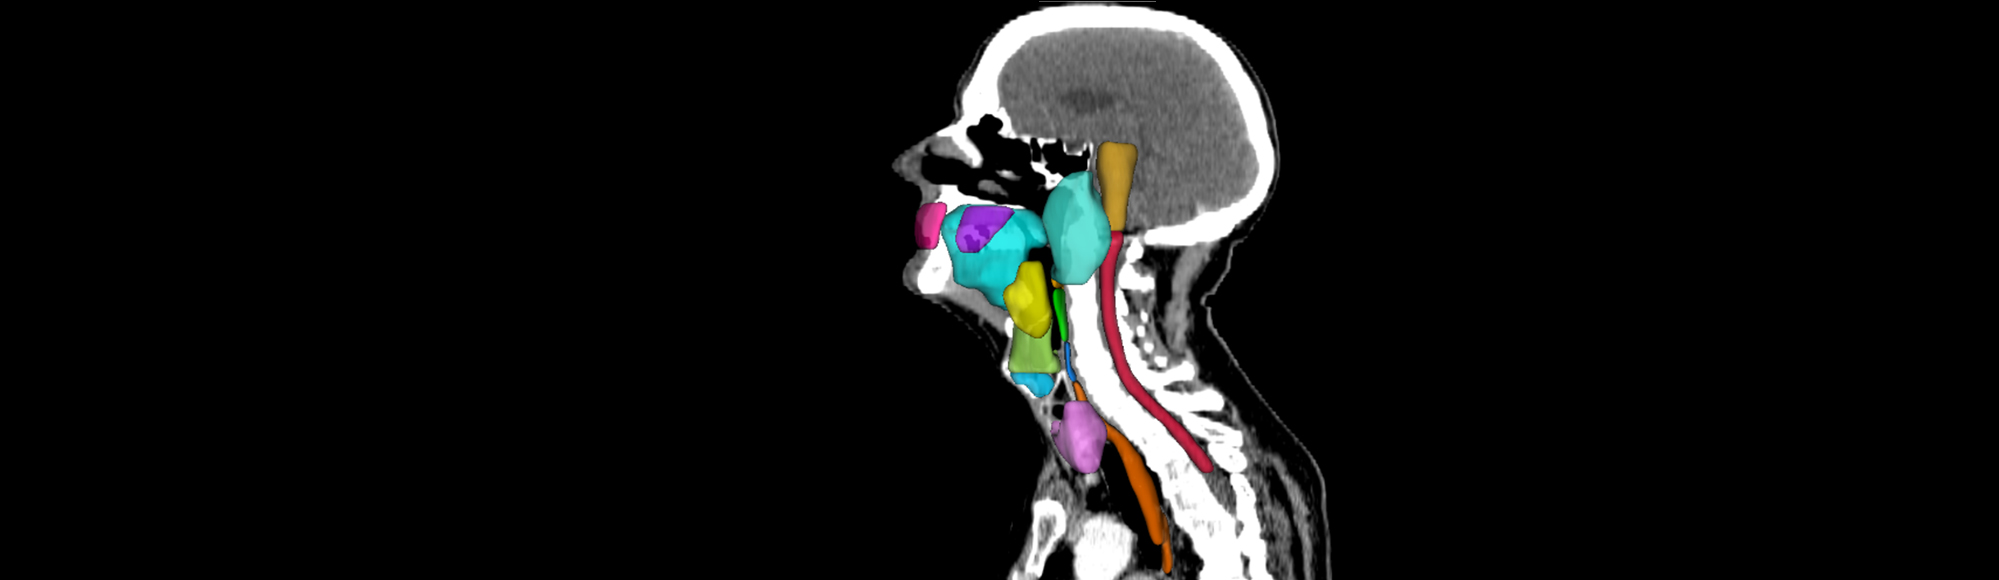

-De AI-modeller, vi vil udvikle i projektet, er såkaldte Foundational Models – store billedgenkendelsesmodeller, der trænes på data fra blandt andet CT- og MR-skanninger. Hvor tidligere AI-løsninger typisk har været designet til én snæver opgave, vil de nye modeller kunne bruges på tværs af flere kliniske formål: fra at identificere tumorer, til at forudsige effekten af behandlingen og støtte opfølgning, fortæller Christian Rønn Hansen.

Modellerne bliver bygget til at kunne håndtere forskellige typer sundhedsdata. Ikke kun billeder, men også for eksempel patientjournaler og tidligere behandlingsforløb, hvilket gør dem mere anvendelige. Derudover lægges der vægt på gennemsigtighed, så læger skal kunne forstå og vurdere, hvordan AI’en kommer frem til sine anbefalinger.

De kommende AI-værktøjer skal blandt andet hjælpe med at afgrænse tumorer før behandlingen, overvåge patientens respons undervejs og identificere risici for senfølger eller tilbagefald efter endt behandling.